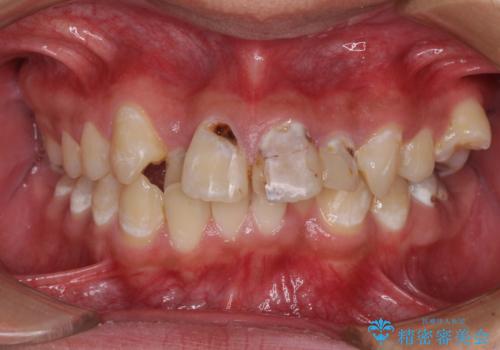

前歯のデコボコとむし歯だらけの歯列 矯正治療と虫歯治療

- むし歯が多く、歯並びも悪いとのことで、以前通院されていたご家族の紹介で来院された患者様です。

口腔内に無頓着であったため、まずはしっかりと歯磨きトレーニングを行い、必要な虫歯治療を行いました。

矯正治療は、むし歯が酷く抜歯が望ましい歯を1本抜歯して、ワイヤー装置にて整えることとしました。